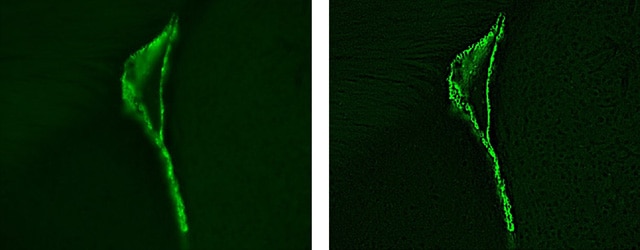

Die linke Aufnahme zeigt die Rohdaten, die durch die Verbindung von fünf horizontal aufgenommenen Bildern und acht vertikal aufgenommenen Bildern erhalten wurden. Die Überlappungsbereiche fallen auf, da der Kontrast unterschiedlich ausgeprägt ist.

Die rechte Aufnahme zeigt im Vergleich dazu ein Bild, das durch die Bildzusammensetzungsfunktion der Modellreihe BZ erzeugt wurde, welche die Kacheleffekte zwischen den verschiedenen Bildern automatisch korrigiert. Diese Überlappungen sind nicht mehr sichtbar. Von der Bildaufnahme bis zur Bildzusammensetzung und -korrektur vergehen durch den Einsatz des Mikroskops BZ weniger als drei Minuten.

(Aufnahmen zur Verfügung gestellt von: Assistenzprofessor Dr. Takehiko Sunabori, Medizinische Fakultät der Universität Keio)